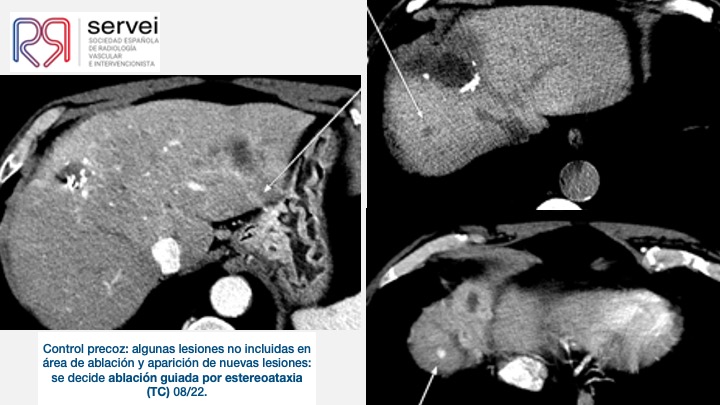

- Ablacion estereoataxia lesiones hepaticas 01

- Ablacion estereoataxia lesiones hepaticas 02

- Ablacion estereoataxia lesiones hepaticas 03

- Ablacion estereoataxia lesiones hepaticas 04

- Ablacion estereoataxia lesiones hepaticas 05

- Ablacion estereoataxia lesiones hepaticas 06

- Ablacion estereoataxia lesiones hepaticas 07

- Ablacion estereoataxia lesiones hepaticas 08

- Ablacion estereoataxia lesiones hepaticas 09

- Ablacion estereoataxia lesiones hepaticas 10

- Ablacion estereoataxia lesiones hepaticas 11

- Ablacion estereoataxia lesiones hepaticas 12

- Ablacion estereoataxia lesiones hepaticas 13

- Ablacion estereoataxia lesiones hepaticas 14